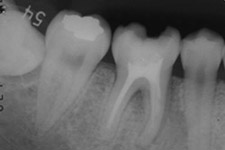

左:移植直後のエックス線写真。

右:移植後1ヶ月。

根管治療直後。歯根が完成している歯を移植歯として用いた場合、歯の神経はつながらないので、このように神経の治療が必要になります。